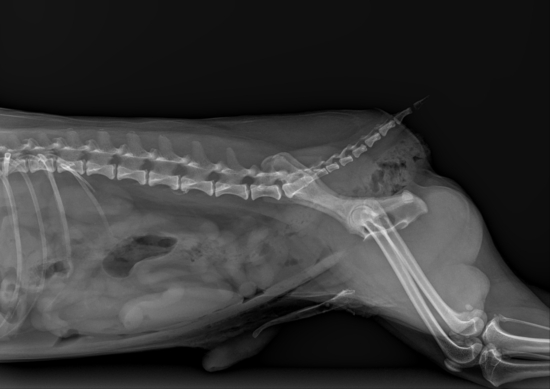

例えば、犬でも猫でも暴れて手術前に検査が出来ない症例もいます。特にノラネコの去勢手術や避妊手術などです。普段、外で生活しているためよくわかりません。昨年こんなことがありました。ノラネコの去勢手術を依頼され、狂暴のため触ることもできません。麻酔をかけ去勢手術を終えて麻酔を覚ましましたが、一向に覚めません。慌てて、血液検査とレントゲン検査を行った所、横隔膜ヘルニアのため換気不全の状態になってしまいました。その後は一命を取留めましたが、心肺蘇生などを行い回復まで時間を要しました。次の写真はその際の写真です。